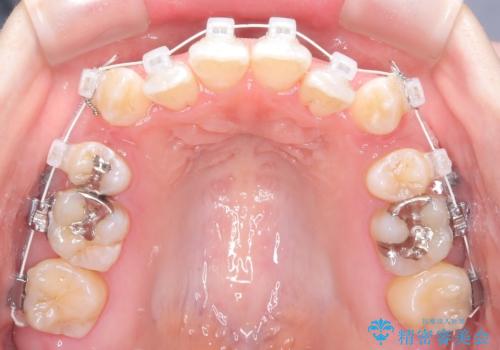

- 前歯のガタガタや八重歯の位置の乱れが気になっていた患者様に対して、ワイヤー矯正を行いました。矯正の過程で、スペースを確保するために上下左右の小臼歯を抜歯し、歯全体のバランスと機能性を考慮しながら理想的な歯列に仕上げました。

抜歯によって確保したスペースを活用し、効率的に歯列を整えました。前歯のガタガタと八重歯が解消され、自然で美しい仕上がりを実現しました。